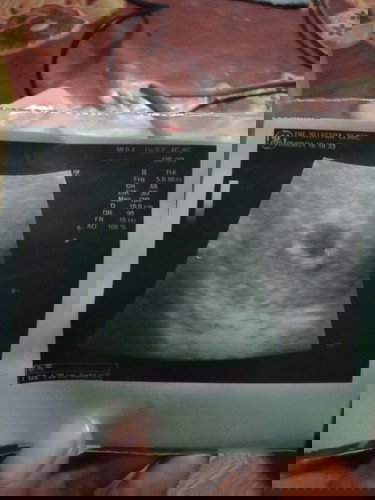

ท้องได้4w4dจะคลอดประมานเดือนใหนค่ะท้องแรกไม่รุ้จิงๆๆค่ะ...ขอบคุนค่ะ

น่าจะปลายมีนา ไม่ก็เมษาค่ะ